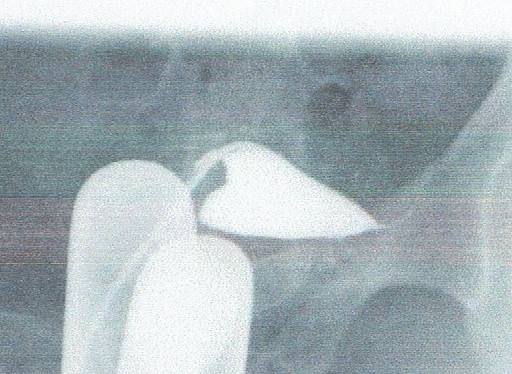

結果は写真のごとく、がっちりと間質部で閉塞していたのです。